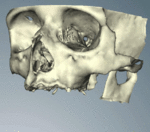

When a more exacting plan is needed beyond clinical judgment, the dentist will make an acrylic guide (called a stent) prior to surgery which guides optimal positioning of the implant. Increasingly, dentists opt to get a CT scan of the jaws and any existing dentures, then plan the surgery on CAD/CAM software. The stent can then be made using stereolithography following computerized planning of a case from the CT scan. The use of CT scanning in complex cases also helps the surgeon identify and avoid vital structures such as the inferior alveolar nerve and the sinus.[17][18](p1199)